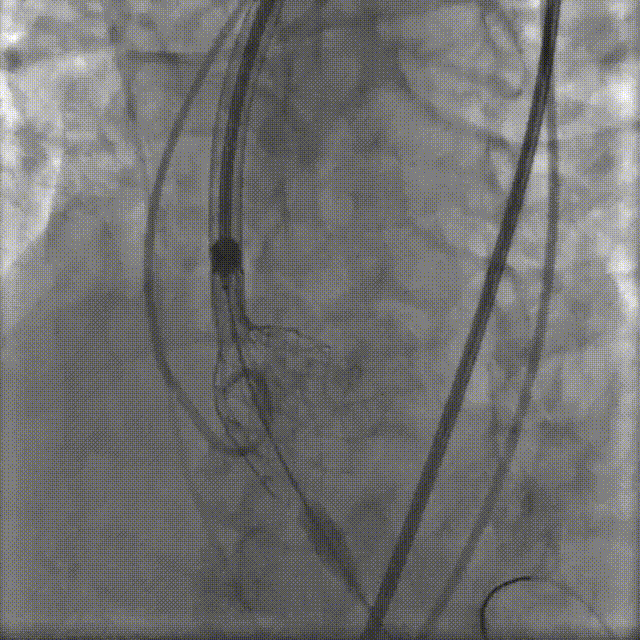

置入猪尾进行根部造影,造影可见根部钙化不均匀,瓣叶活动度低,冠脉灌注良好。

根部造影

22mm球囊预扩,轻微腰征,冠脉显影良好,无造影剂渗漏。

22mm球囊预扩

TaurusElite AV29号瓣膜定位及释放。瓣膜初始定位-3位,开花后120次起搏,释放到工作位后造影显示锚定充足,位置良好,冠脉未见遮挡,继续缓慢旋转手柄,轻推输送器,瓣膜逐一脱钩,顺利释放。

瓣膜初始定位

瓣膜释放过程

工作位造影

瓣膜脱钩

释放后多体位观察造影,提示瓣膜位置良好,展开良好,双侧冠脉未见遮挡,微量瓣周漏。

最终造影